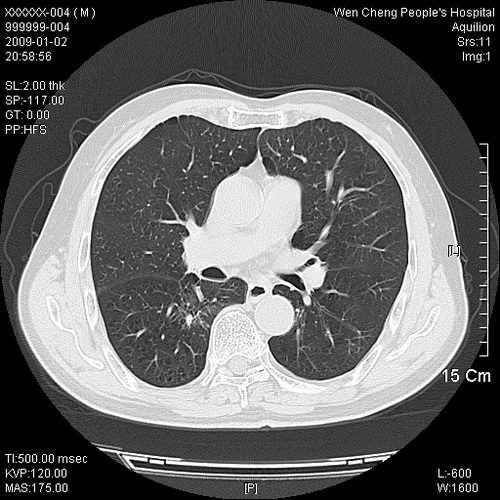

男性,73岁,有慢支病史,肿瘤系列标志物检验正常,血沉及血常规正常

右肺下叶背段小片状 磨玻璃样模糊影,内见血管及含气支气管像,支气管管壁增厚。考虑:慢性炎症!

支气管炎,小叶气肿,右下肺局限性炎症并轻度支气管扩张冠脉钙化。

右肺下叶背段小片状 实性与磨玻璃样影,内见血管及含气支气管像,支气管管壁增厚,边缘见长毛刺影。考虑:慢性炎症或肿瘤!建议抗炎治疗复查,密切观察随访!

右肺下叶片团状影内见扩张的含气支气管和支气管管壁增厚,其周有磨玻璃样模糊影和长毛刺。考虑慢性炎症可能性大。

2、右肺下叶片团状影内见扩张的含气支气管和支气管管壁增厚,其周有磨玻璃样模糊影和长毛刺。考虑周围型肺ca可能,结核不排。

机化性肺炎 , 左右冠状动脉钙化。